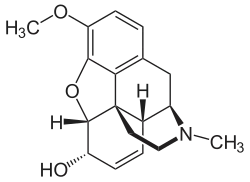

Codein (= 3-Methylmorphin) ist durch eine Methylierung etwas lipophiler als Morphin

Codein (= 3-Methylmorphin) ist durch eine Methylierung etwas lipophiler als Morphin -

Das Diffusionsvermögen eines Moleküls durch die Endothelien der Blut-Hirn-Schranke wird vor allem durch seine Fettlöslichkeit (Lipophilie) und Größe bestimmt. Durch eine Modifizierung des Moleküls mit lipophilen Gruppen kann deshalb eine verbesserte Gehirngängigkeit erreicht werden.[33] Ein klassisches Beispiel hierfür ist die Di-Acetylierung des Naturstoffes Morphin zu Diacetylmorphin (Heroin). Heroin (log P=1,12) zeigt gegenüber Morphin (log P=0,2) eine über 25fach höhere Aufnahme im Gehirn (siehe dazu: Tabelle 1).[34] Entsprechende Ergebnisse werden beim Brain-Uptake-Index (BUI) für radioaktiv markiertes Morphin, Codein und Heroin erhalten, das in die Halsschlagader injiziert wird. Für Morphin liegt der BUI unterhalb der Nachweisgrenze, bei Codein bei 24 % und für Heroin bei 68 %.[35]